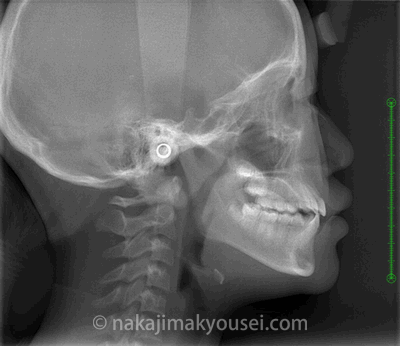

2、側貌セファロ

下の横顔レントゲンから顎の位置関係を診断します。たとえばこの写真のように前歯が反対に噛んでいる人であれば、その原因が頭の位置に対して下あごが前に位置していることによるものか、上あごが後ろに位置しているからなのか、上下の顎の位置には問題がなくて上下の歯の傾きが悪いことによるものかを診断するのです。